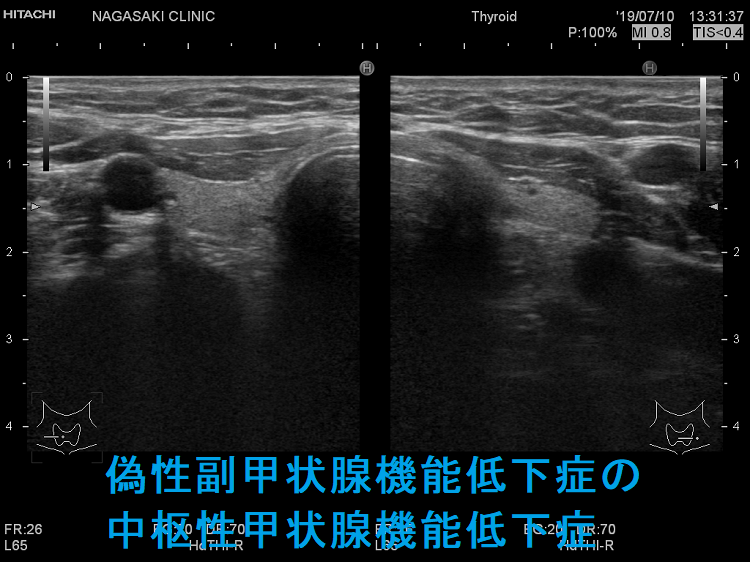

偽性副甲状腺機能低下症で甲状腺機能低下症

偽性副甲状腺機能低下症Ⅰa型における出生時の先天性甲状腺機能低下症の頻度は8〜34%(Horm Res Paediatr. 2015;83(2):111-7.)。

偽性副甲状腺機能低下症に伴う甲状腺機能低下症は、通常軽度で、甲状腺腫大を認めない事が多いです(Best Pract Res Clin Endocrinol Metab. 2017 Mar;31(2):161-173.)。